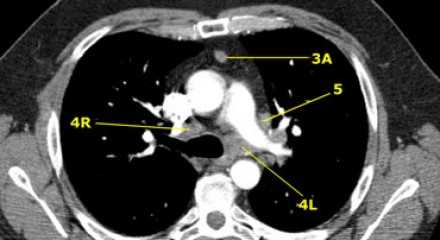

Лимфатические узлы 3 группы не примыкают к трахее в отличии от лимфатических узлов 2 группы. Они подразделюятся на: 3А кпереди от сосудов 3Р позади пищевода/превертебрально Они не доступны при медиастиноскопии. 3Р группа может быть доступна при чреспищеводной эхокардиографии.

На изображении слева 3А узел в преваскулярном пространстве. Обратите внимание так же на ниже расположенные паратрахеальные узлы справа относящиеся к 4R группе.

4R. Правые нижние паратрахеальные лимфатические узлы

- Верхняя граница: пересечение нижнего края левой плечеголовной вены с трахеей.

- Нижняя граница: нижний края непарной вены. 4R узлы распространяются до левого края трахеи.

На изображении слева мы видим 4R паратрахеальные узлы. Кроме того здесь представлен узел кнаружи от дуги аорты, то есть 6 группы.

4L. Левые нижние паратрахеальные лимфатические узлы

4L узлы расположенные слева от левой стенки трахеи, между горизонтальными линиями проведенными касательно верхней стенке дуги аорты и линией проходящей через левый главный бронх на уровне верхнего края верхнедолевого бронха. Они включают паратрахеальные узлы расположенные кнутри от артериальной связки.

Узлы 5 группы (аортопульмонального окна) расположены кнаружи от артериальной связки.

На левом изображении над уровнем легочного ствола представлены нижние паратрахеальные узлы слева и справа, так же здесь представлены узлы 3 и 5 групп.

Изображение слева выше уровня карины. Слева от трахеи 4L узлы. Обратите внимание что они расположены между легочным стволом и аортой, но не в аортопульмональном окне, потому что они лежат медиальнее артериальной связки. Лимфатические узлы латеральнее легочного ствола относятся к 5 группе.